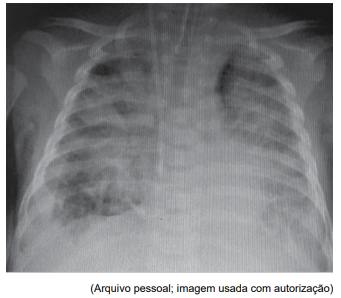

Um paciente de 7 anos encontra-se internado em UTI

pediátrica devido a queimaduras que acometem 40%

da superfície corpórea. Está intubado e em ventilação

mecânica, sem necessidade de drogas vasoativas. Nas

últimas 24 horas, apresentou piora ventilatória importante

(radiografia de tórax a seguir). Não apresenta disfunção

hemodinâmica grave; ecocardiograma funcional sem

alterações.

No momento, encontra-se em modo assistido-controlado, pressão controlada, com os seguintes parâmetros: PEEP: 8 cmH2 O; frequência respiratória: 30 irpm; pressão controlada (acima do PEEP): 18 cmH2 O; tempo inspiratório: 0,8 s; FiO2 : 100%; média de volume corrente: 7 mL/kg; pressão média das vias aéreas (Paw): 15 cmH2 O. Gasometria arterial: pH: 7,24; pCO2 : 60; pO2 : 100; bic: 23; BE: –2; SatO2 : 84%.

Com base nos dados apresentados, assinale a alternativa que contenha o valor mais adequado do Índice de Oxigenação (IO) e a melhor conduta ventilatória a ser instituída nesse momento.